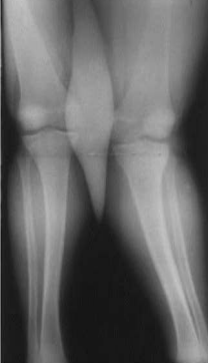

Fig. 4 Clinical appearance (A) and standing anteroposterior radiograph (B) of a 12-yearold child with chronic renal failure. Note the distal femoral physeal irregularities. Genu valgum is the most common skeletal manifestation of renal osteodystrophy